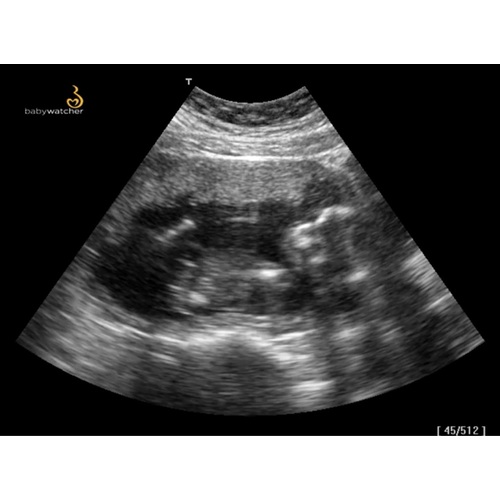

Dat kan ik zeker even doen mijn echo apparatuur begon vandaag te storen met slecht beeld babywatcher gaat morgen van afstand probleem op lossen en krijg een extra dag ik zal morgen dan even een echo foto hier uploaden

Ik vond het best wel duidelijk, vooral als hij veel beweegt! Maar die kan ik niet uploaden, wel heel leuk om terug te kijken

Wij krijgen een dag extra gisteren deed het beeld ineens super raar en vandaag sloeg de apparaat niks op helaas. Ze zijn heel flexibel als je een probleem hebt